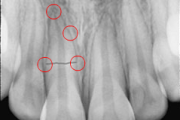

Krooni murrud